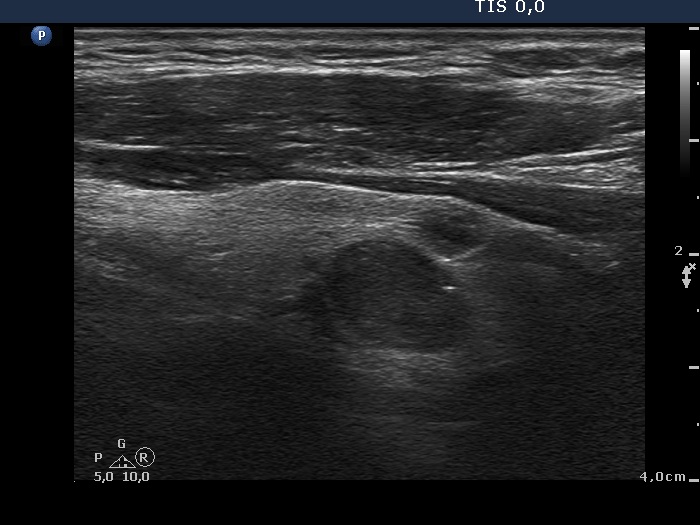

Ultrasonography. The right thyroid was composed of multiple discrete lesions with different echogenicities. The lobe was extremely enlarged with the dimension of 55x65 xminimum 120 mm (width, depth, and length, respectively) and spread retotracheal and substernal. The lower pole of the lobe could not be visualized while swallowing. The left thyroid was normal-sized and contained several hypoechogenic lesions. There was a moderately hypoechogenic nodule in the right lobe. The lesion presented neither halo nor perinodular blood flow.